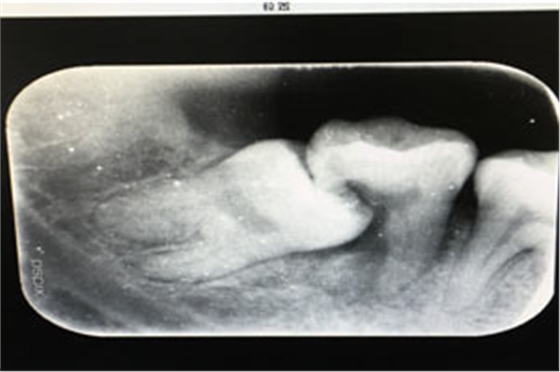

圖2.術(shù)前的x線根尖片影像檢查:47遠中牙根吸收。